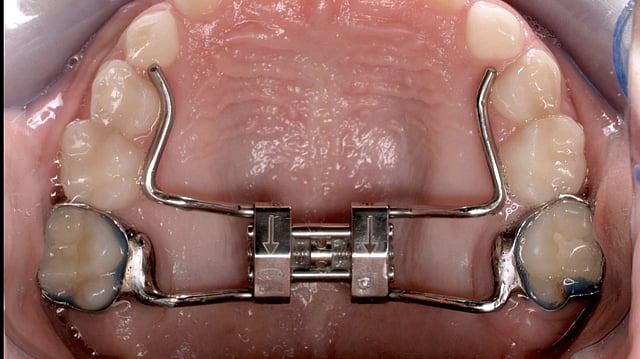

Hyrax rapid palatal expander. Ian Furst, CC BY-SA 4.0, via Wikimedia Commons

• Hyrax expander: A common tooth-borne device activated with a screw